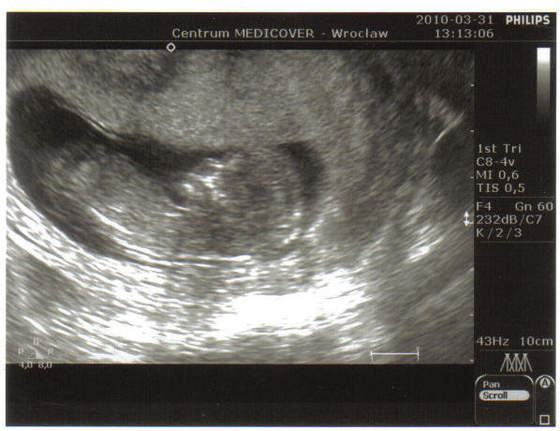

Znamy już płeć. Właśnie na tym USG mały pokazał pisiorka i to dwa razy. Lekarz nie miał żadnych wątpliwości:-)

To nasz (na 99%) Maciuś pod koniec 13 tygodnia. Tylko na koniec badania jak lekarz odpalił 4D to dzidziuś się pogniewał i odwrócił pleckami :D